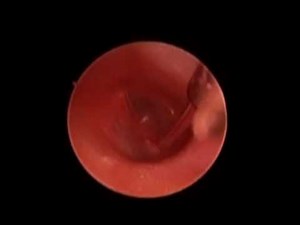

Right Endoscopic PE Tube Placement - EndoEarScape

已浏览 1067 次

2012年8月20日

YouTube

EndoEarScape

0:33

Ear Tube Placement (Endoscopic)

已浏览 155 次

2019年8月13日

Jay Young MD

3:08